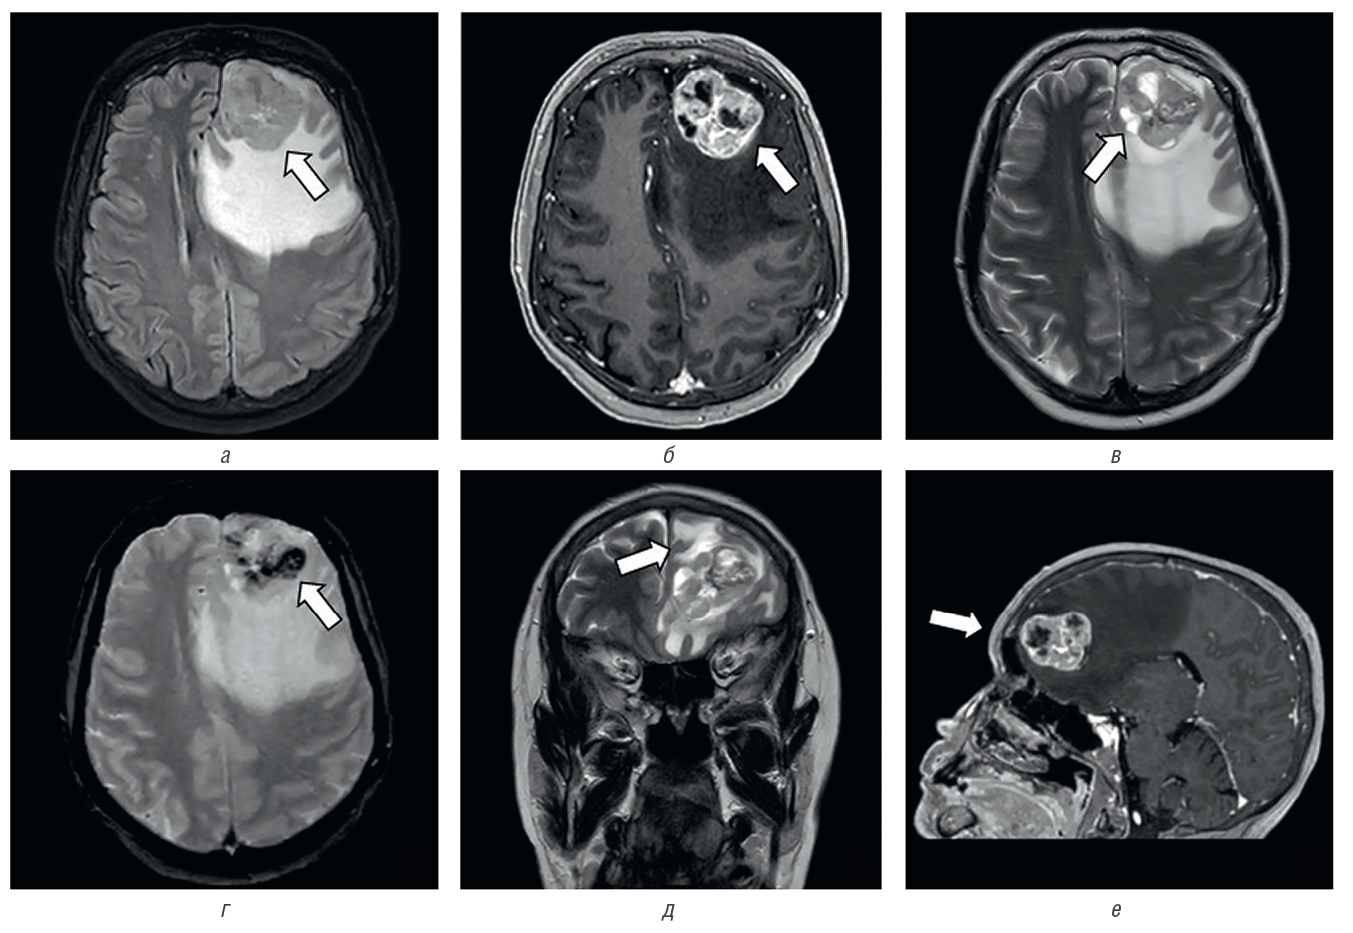

Anamnesis morbi: со слов пациентки, в мае 2019 г. заметила новообразование на коже лба, которое никак не беспокоило. В последние два года при расчесывании стала замечать образование на коже волосистой части головы, которое периодически кровоточило. В начале 2022 г. стала испытывать головную боль диффузного давящего характера, в августе 2022 г. по результатам проведения МРТ ГМ выявлено объемное образование левой лобной доли, интенсивно накапливающее контраст с наличием масс-эффекта на передние рога боковых желудочков, с зоной массивного перифокального отека (рис. 2).

Рис. 2. МРТ головного мозга. Объемное образование левой лобной области: a — МРТ в режиме FLAIR в аксиальной проекции, определяется объемное образование гетерогенно-гиперинтенсивной структуры с неровными контурами (стрелка) и выраженным перифокальным отеком, срединные структуры и боковые желудочки деформированы, смещены; б — МРТ в режиме T1 ISO с контрастным усилением в аксиальной проекции, отмечается активное неоднородное накопление контрастного препарата в структуре опухоли (стрелка); в — МРТ в режиме Т2 в аксиальной проекции, отмечаются жидкостные (некротические?) включения в структуре объемного образования (стрелка); г — МРТ в режиме Т2GRE* в аксиальной проекции, определяются включения отложений продуктов биодеградации гемосидерина в структуре объемного образования (стрелка); д — МРТ в режиме Т2 в корональной проекции, отмечается распространенная зона вазогенного отека вещества головного мозга (стрелка); е — МРТ в режиме T1 ISO с контрастным усилением в сагиттальной проекции (стрелка)

Fig. 2. MRI of the brain. Volumetric formation of the left frontal area; a — MRI in FLAIR mode in axial projection, the volumetric formation of a heterogeneous hyperintensive structure with uneven contours (arrow) and pronounced perifocal edema is determined, the median structures and lateral ventricles are deformed, displaced; б — MRI in T1 ISO mode with contrast enhancement in axial projection, there is an active heterogeneous accumulation of contrast agent in the tumor structure (arrow); в — MRI in T2 mode in axial projection, liquid (necrotic?) inclusions in the structure of volumetric education (arrow); г — MRI in the T2GRE* mode in the axial projection, inclusions of deposits of hemosiderin biodegradation products in the structure of volumetric formation are determined (arrow); д — MRI in the T2 mode in the coronal projection, there is a common area of vasogenic edema of the brain substance (arrow); е — MRI in T1 ISO mode with contrast enhancement in sagittal projection (arrow)